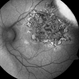

- serpiginous choroiditis

- Imaging device

- Fundus camera

- Serpiginous choroiditis, right eye #1. Advanced pigmented scar formation ( fovea involved).